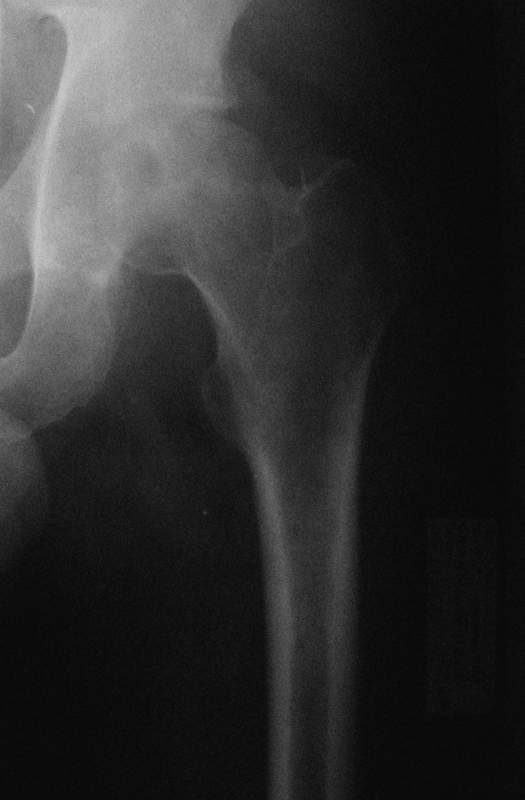

Уважаемые коллеги! Помогите с дифф. диагнозом и тактикой лечения.

Молодой человек, 37л. Начало заболевания сентябрь 2007, резкие боли в области лев.

тазобедренного сустава, повышение температуры до 39 гр., в течение недели, лабораторные

данные: лейкоцитоз со сдвигом влево. Посев крови на стерильность возбудителя не выявил. По

данным Рг, РКТ выставлен диагноз: Левосторонний коксит? Асептический некроз? Проводилось

лечение: цефсон в/в неделю, иммобилизация кокситной повязкой 1 мес. Обратился повторно 10

дней назад с жалобами на сильные боли в левом тазобедренном суставе, белая кровь

нормограмма, СОЭ 46 мм/ч. На сегодняшний день: болей не отмечает. Лаб.данные: белая кровь

нормограмма, СОЭ 30 мм/ч. Рентген и РКТ прилагаем.